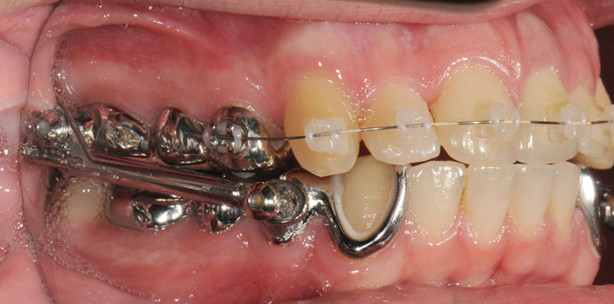

Bei der mit bukkalen Brackets durchgeführten Standardtherapie wird die Herbst-Apparatur in der ersten Phase mit Brackets an den Frontzähnen im Oberkiefer kombiniert (Abb. 19). Es werden im Normalfall keine Brackets im Unterkiefer verwendet, da diese nur die Hygiene erschweren und die Reparaturanfälligkeit erhöhen. Der linguale Verbindungsbügel sollte die Frontzähne nicht berühren (Abb. 20). Die Eckzähne werden nur dezent gefasst und demzufolge ohne aufgeschweißte Brackets versehen (Abb. 21).

Wir bevorzugen selbst beim Deckbiss die einzeitige Verfahrensweise, d.h. die Vorbehandlung zur Proklination der Frontzähne entfällt, da es durch die Bissöffnung durch den beim Deckbiss vergesellschafteten tiefen Biss letztendlich auch zu einer vergrößerten Frontzahnstufe kommt und somit der Effekt der Vorverlagerung bei Einstellung einer Kopfbissrelation festzustellen ist (Abb. 22). Die Überkorrektur bzw. Rezidivprophylaxe erfolgt durch Lückenbildung zwischen den oberen Eckzähnen und den ersten Prämolaren, eine Mesialrelation der Molaren wird eingestellt (Abb. 23). Dadurch können wir auf die Einstellung eines frontalen Kreuzbisses verzichten, die Patienten werden niemals weiter nach anterior als in Kopfbissrelation geführt.